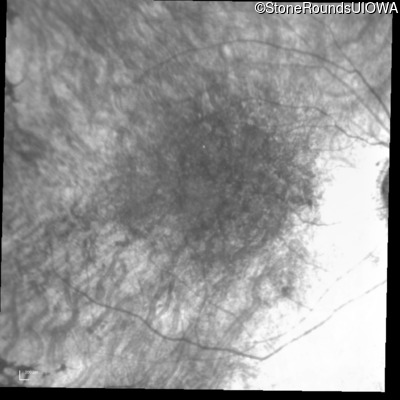

Infrared Fundus Photograph - Right - 20/60 +1 sc

Exemplar